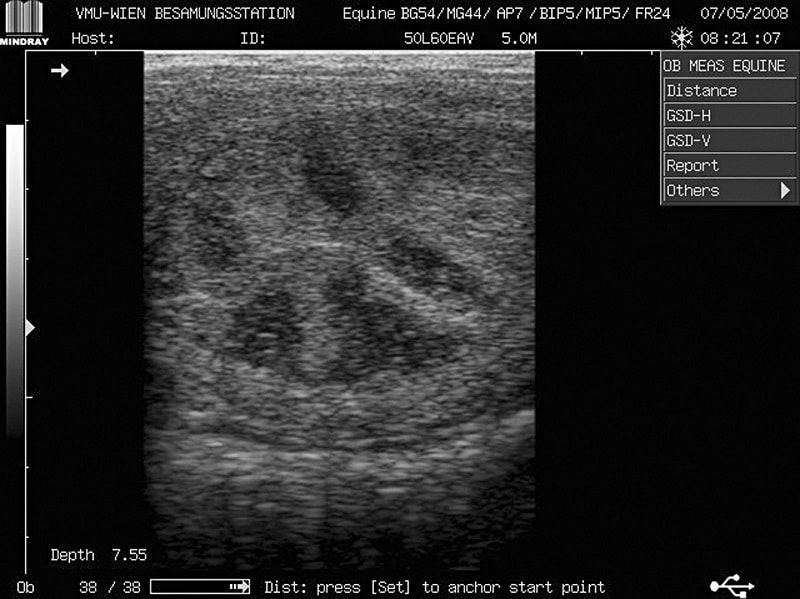

radspeichenstruktur_aurich[1]